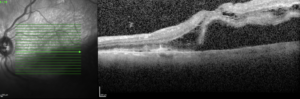

Diagnostic

Le diagnostic de décollement de rétine se fait au fond d’œil. On peut s’aider de l’OCT pour juger du statut décollé ou non de la macula. On peut s’aider d’une échographie mode B en cas de trouble des milieux.

Le diagnostic

Son diagnostic est fait à l’OCT (Optical Coherence Tomography).